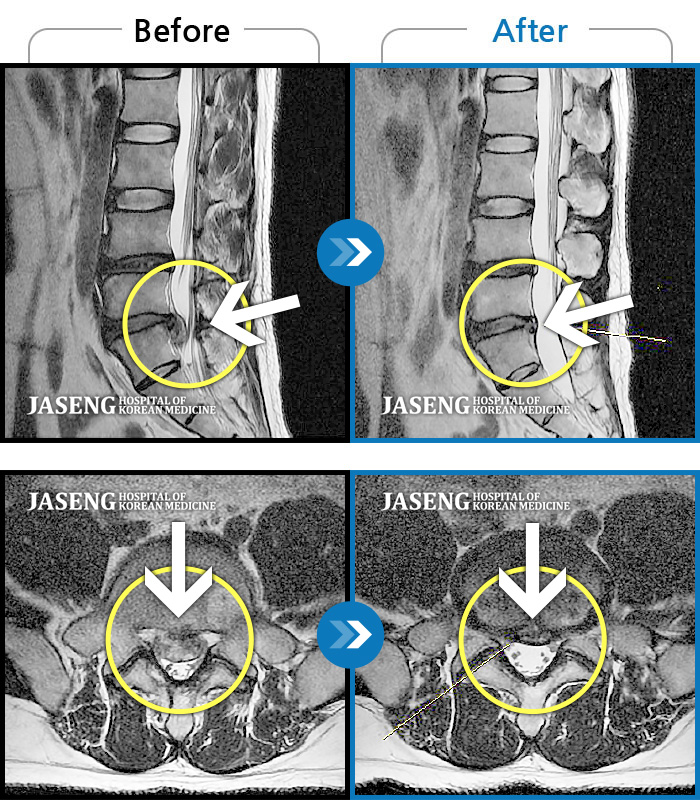

처음 내원 시 허리와 좌측 골반이 많이 아프고, 좌측 다리로 저림과 감각 저하가 있어서 보행이 원활하지 못했으며, 야간통으로 잠도 못 자고 통증 심하여 정상적인 활동이 힘든 상태셨습니다.

2023.09.16 ~ 2024.09.24